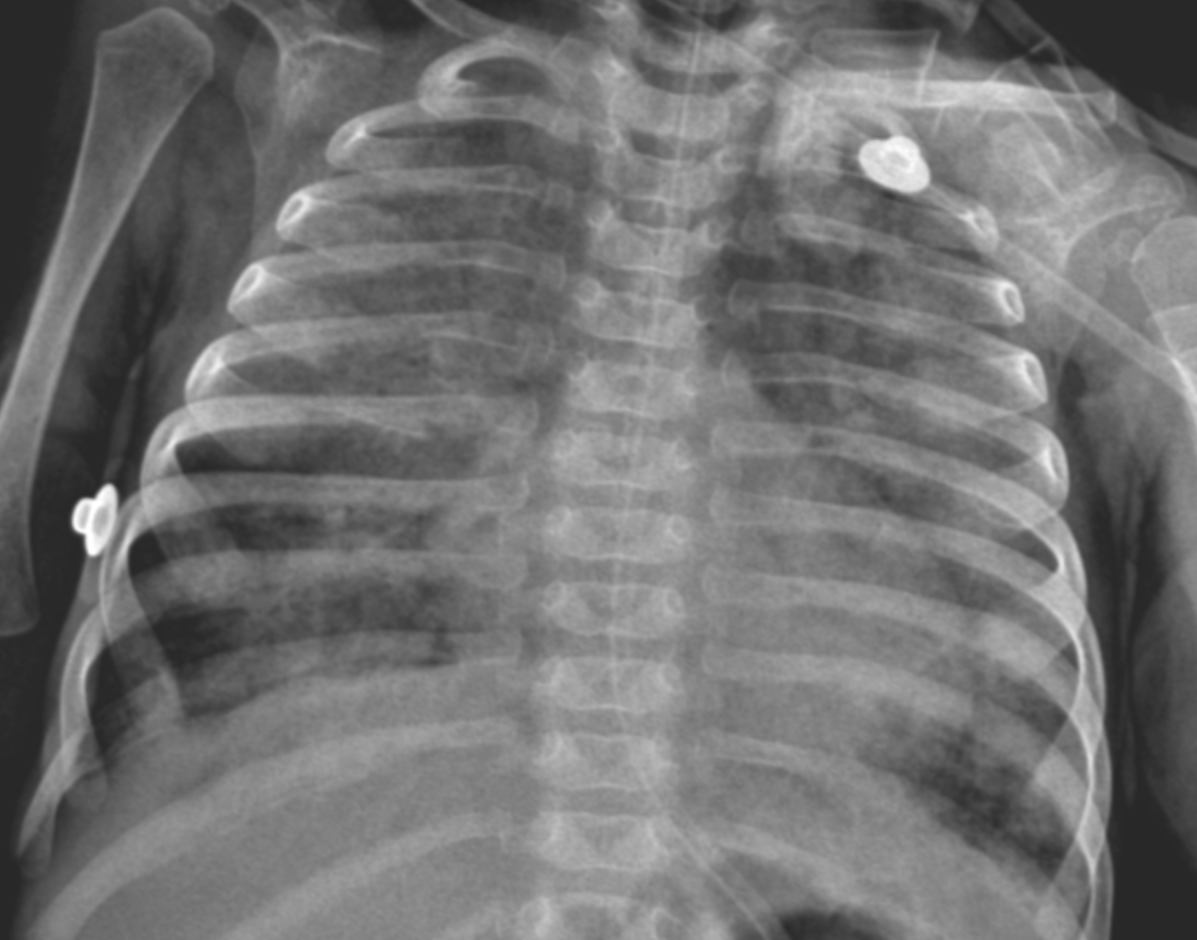

Initial diagnostic workups for immunodeficiency and metabolic diseases were normal; however, a sweat test could not be performed due to the patient's poor general condition and malnutrition. Echocardiography showed no cardiac disease, and abdominal ultrasound was normal. Due to parental consanguinity and a history of a sibling death at 9 months with similar clinical symptoms, a congenital genetic disease with associated interstitial lung disease (ILD) was primarily suspected. Consequently, clinical genetics was consulted, and Whole Exome Sequencing (WES) analysis was initiated. The severity of hypoxemia was assessed using the Oxygen Saturation Index (OSI) and the patient was diagnosed with PARDS based on acute hypoxemia, an OSI of 25, and chest X-ray findings showing new-onset bilateral diffuse alveolar infiltration and pulmonary parenchymal edema (1,2) (Figure 1). Initial axial chest computed tomography was performed at ICU admission, demonstrating diffuse bilateral ground-glass opacities and consolidations (Figure 2A, 2B). Thoracic ultrasound identified bilateral pleural effusions (7 mm on the right and 10 mm on the left). Due to elevated acute phase reactants (WBC: 57 x 109/L, CRP: 33 mg/L), antibiotic therapy was initiated with Vancomycin and Meropenem, alongside appropriate symptomatic PARDS management.

Initial chest X-ray showing diffuse bilateral alveolar infiltrates

Figure 1. Initial chest X-ray. Chest radiograph obtained before bronchoscopic intervention showing diffuse bilateral alveolar infiltrates consistent with severe pediatric acute respiratory distress syndrome.